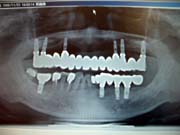

<インプラントの

実際のレントゲン画像>

インプラント治療とは、歯の抜けたところに人工の歯根(インプラント)を植え、顎の骨としっかり固定させた後に、人工の歯を装着したものです。